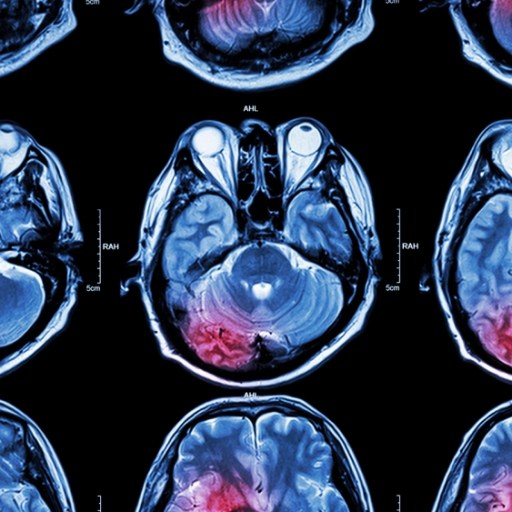

post-stroke dementia

Researchers look to an FDA-approved drug ingredient that can "scoop-up" and store cholesterol and possibly stave off post-stroke dementia.